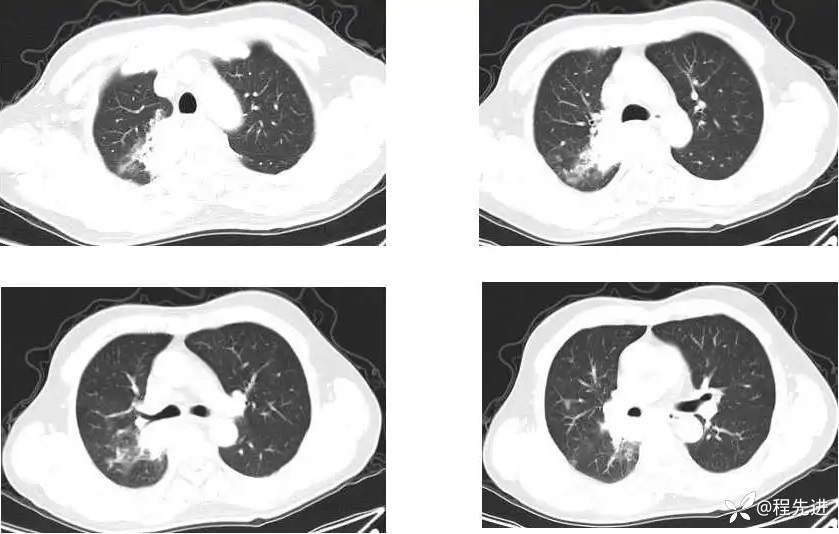

主 诉:间断咳嗽、痰中带血1月,发现肺门占位8天

现病史:患者1月前受凉后出现咳嗽咳痰,痰中见血丝,量少,伴有右侧胸痛不适,夜间有盗汗,无发热,在社区予以抗感染治疗3天(具体用药不详),胸痛症状缓解,但仍间断出现痰中带血,未再行诊治;8天前检查发现肺门占位;患者近2日咯血量较前增多,每日约4-5口,为鲜红色

CT增强: